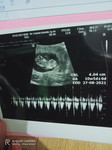

Hamil sayah udh 6week tp sayah sakit perut bawah apa kah normal π₯Ί